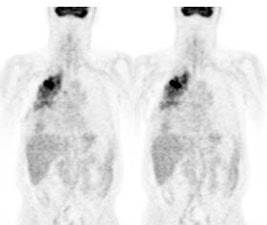

Lung cancer 1 cm lesion: The images below were from a patient with a 1 cm sized right upper lobe lung cancer. Note the excellent conspicuity of the lesion on FDG PET imaging. The exam was acquired using an ECAT EXACT PET scanner (CTI) with 5 min/bed emission and 2 min/bed segmented transmission. OS-EM iterative reconstruction was used for exam reconstruction. Case courtesy of Mallinckrodt Institute of Radiology/ Barnes Hospital, St. Louis and CTI PET Systems, Inc. |